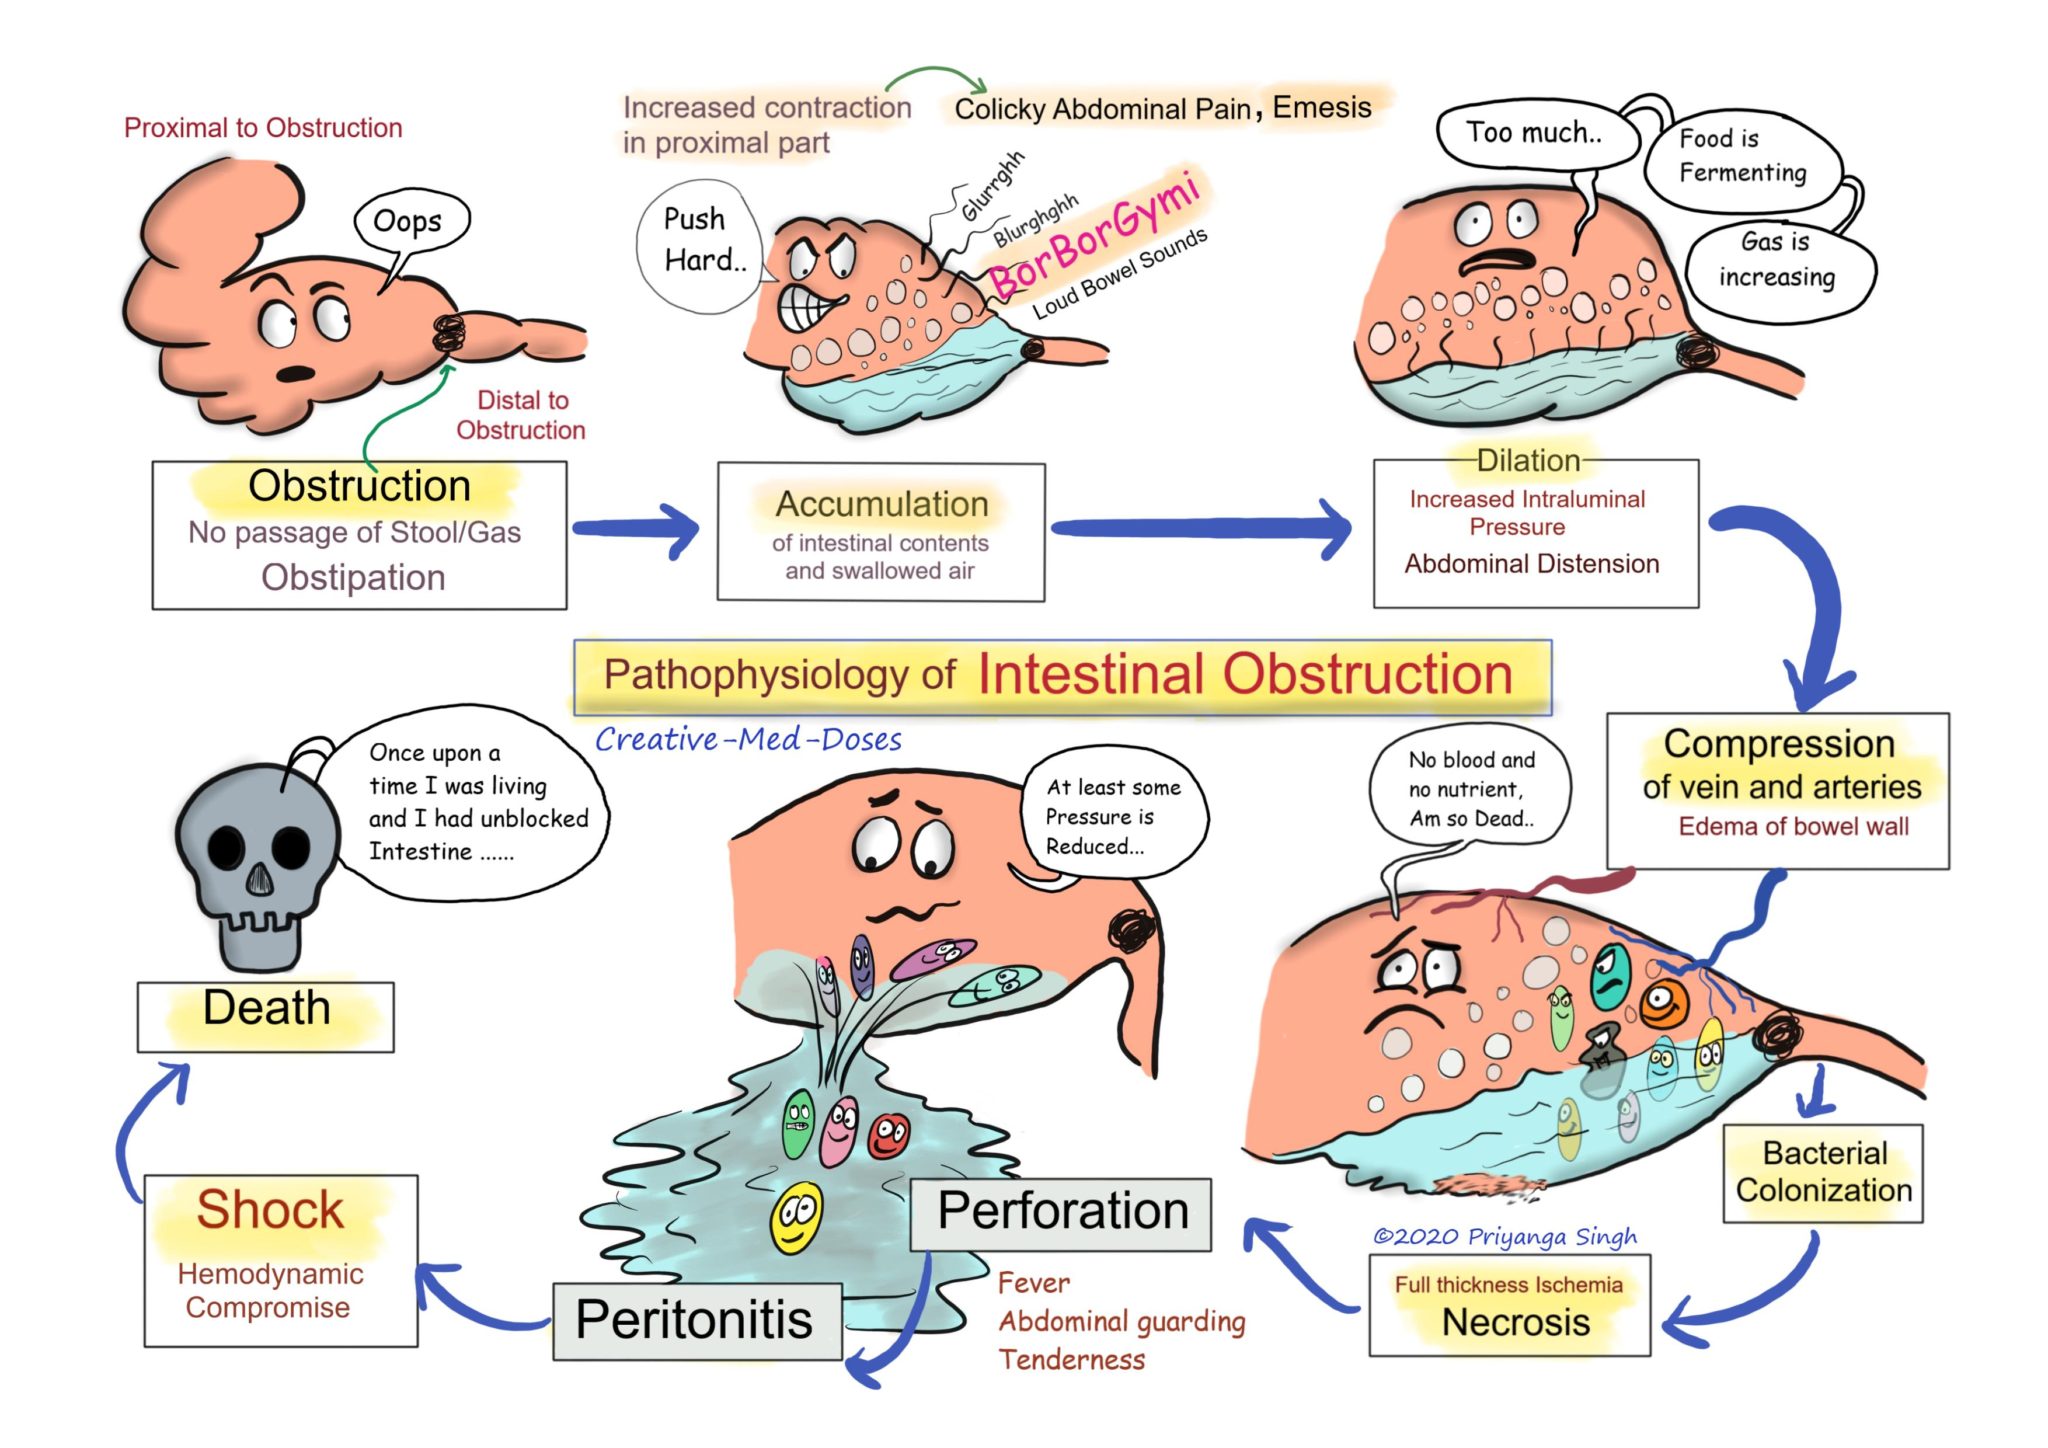

Acute Intestinal Obstruction Pathophysiology Creative Med Doses

Intestinal Obstruction

Intestinal Obstruction

Intestinal Obstruction